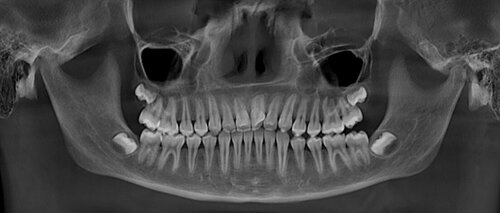

В среднем доза лучевой нагрузки при конусно-лучевой компьютерной томографии (КЛКТ) составляет от 40 до 120 мкЗв (микрозиверт).

Однако...